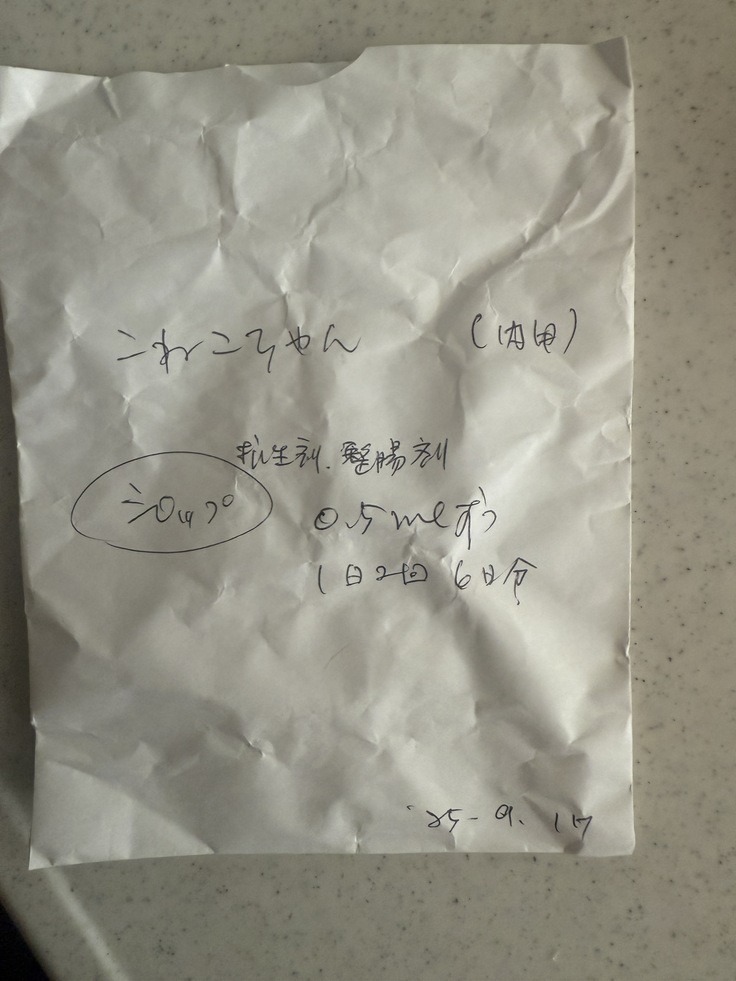

熱が40.7℃、少しの脱水がありこの時は風邪との診断で抗生剤を6日間いただきました。

シリンジで嫌がるところを頑張って飲んでもらっても効果がなく、9月15日〜全くご飯を食べない状態は変わらず、さらに元気もなくなり寝たきり生活に。

6日分もらいましたが23日が祝日だったため22日に再診へ。

すぐに血液検査など詳しい検査をしていただき、出た結果です。

タンパク質からの計算式に基づいて、この時点でおそらくFIPで間違いないだろうとの診断でした。

一刻も早く治療を開始したほうがいいとのことで、23日夜から投薬を開始しました。